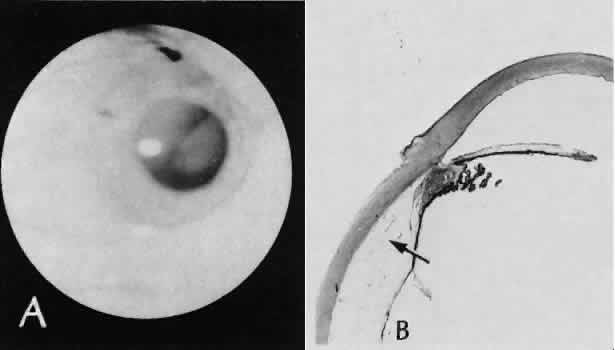

Wound healing of the posterior uveal tract follows the general principles for healing of vascularized tissue. The iris, however, heals differently. When the iris wound is perpendicular to its circumferential ridges, such as in a typical peripheral iridectomy or iridotomy, the cut edges pull apart. Granulation tissue does not form to close iridectomy incisions probably because of the inhibitory effect of the aqueous flowing through the opening of these small incisions. Iridotomies created by argon laser (Fig. 10) may be anatomically closed by apparent migration of iris pigment epithelium.36,37

Fig. 10. Scanning electron micrograph of the posterior surface of the iris in a case of angle closure glaucoma treated with argon laser iridotomy. Centrally, there are three areas of penetration of iris tissue. Iris pigment epithelium has been lost for a considerable distance from the actual opening (arrow). Normal iris pigment epithelium is present peripherally.